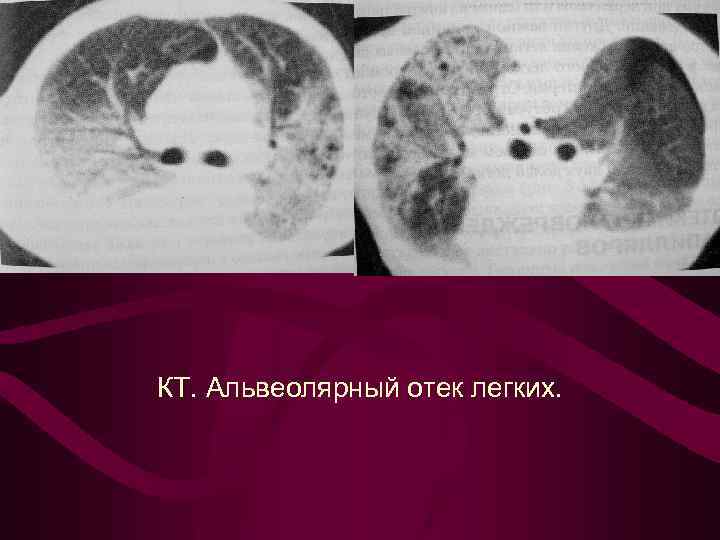

Альвеолярный отек характеризуется появлением участков безвоздушной легочной ткани различной формы и размеров, от небольших инфильтратов с нечеткими контурами до уплотнения значительной части легкого локализация безвоздушных участков легочной ткани вне зависимости от долевого и сегментарного строения легкого Характерно:

Альвеолярный отек характеризуется появлением участков безвоздушной легочной ткани различной формы и размеров, от небольших инфильтратов с нечеткими контурами до уплотнения значительной части легкого локализация безвоздушных участков легочной ткани вне зависимости от долевого и сегментарного строения легкого Характерно:

Типичные рентгенологические признаки (кардиогенного) альвеолярного отека: инфильтратоподобных теней средней интенсивности в центральных задних отделах легких с двух сторон перераспределение легочного кровотока (цефализация) значительное расширение, уплотнение и нечеткость очертания корней легких линии Керли, перибронхиальные муфты, плевральный выпот быстрая динамика как при прогрессировании, так и при обратном развитии процесса (часы - 1 -2 суток) расширение размеров сердца и сосудистой ножки

Типичные рентгенологические признаки (кардиогенного) альвеолярного отека: инфильтратоподобных теней средней интенсивности в центральных задних отделах легких с двух сторон перераспределение легочного кровотока (цефализация) значительное расширение, уплотнение и нечеткость очертания корней легких линии Керли, перибронхиальные муфты, плевральный выпот быстрая динамика как при прогрессировании, так и при обратном развитии процесса (часы - 1 -2 суток) расширение размеров сердца и сосудистой ножки

КТ. Альвеолярный отек легких.

КТ. Альвеолярный отек легких.